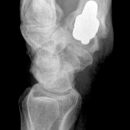

TEP Daumensattelgelenk

Es wurden keine Bilder gefunden.